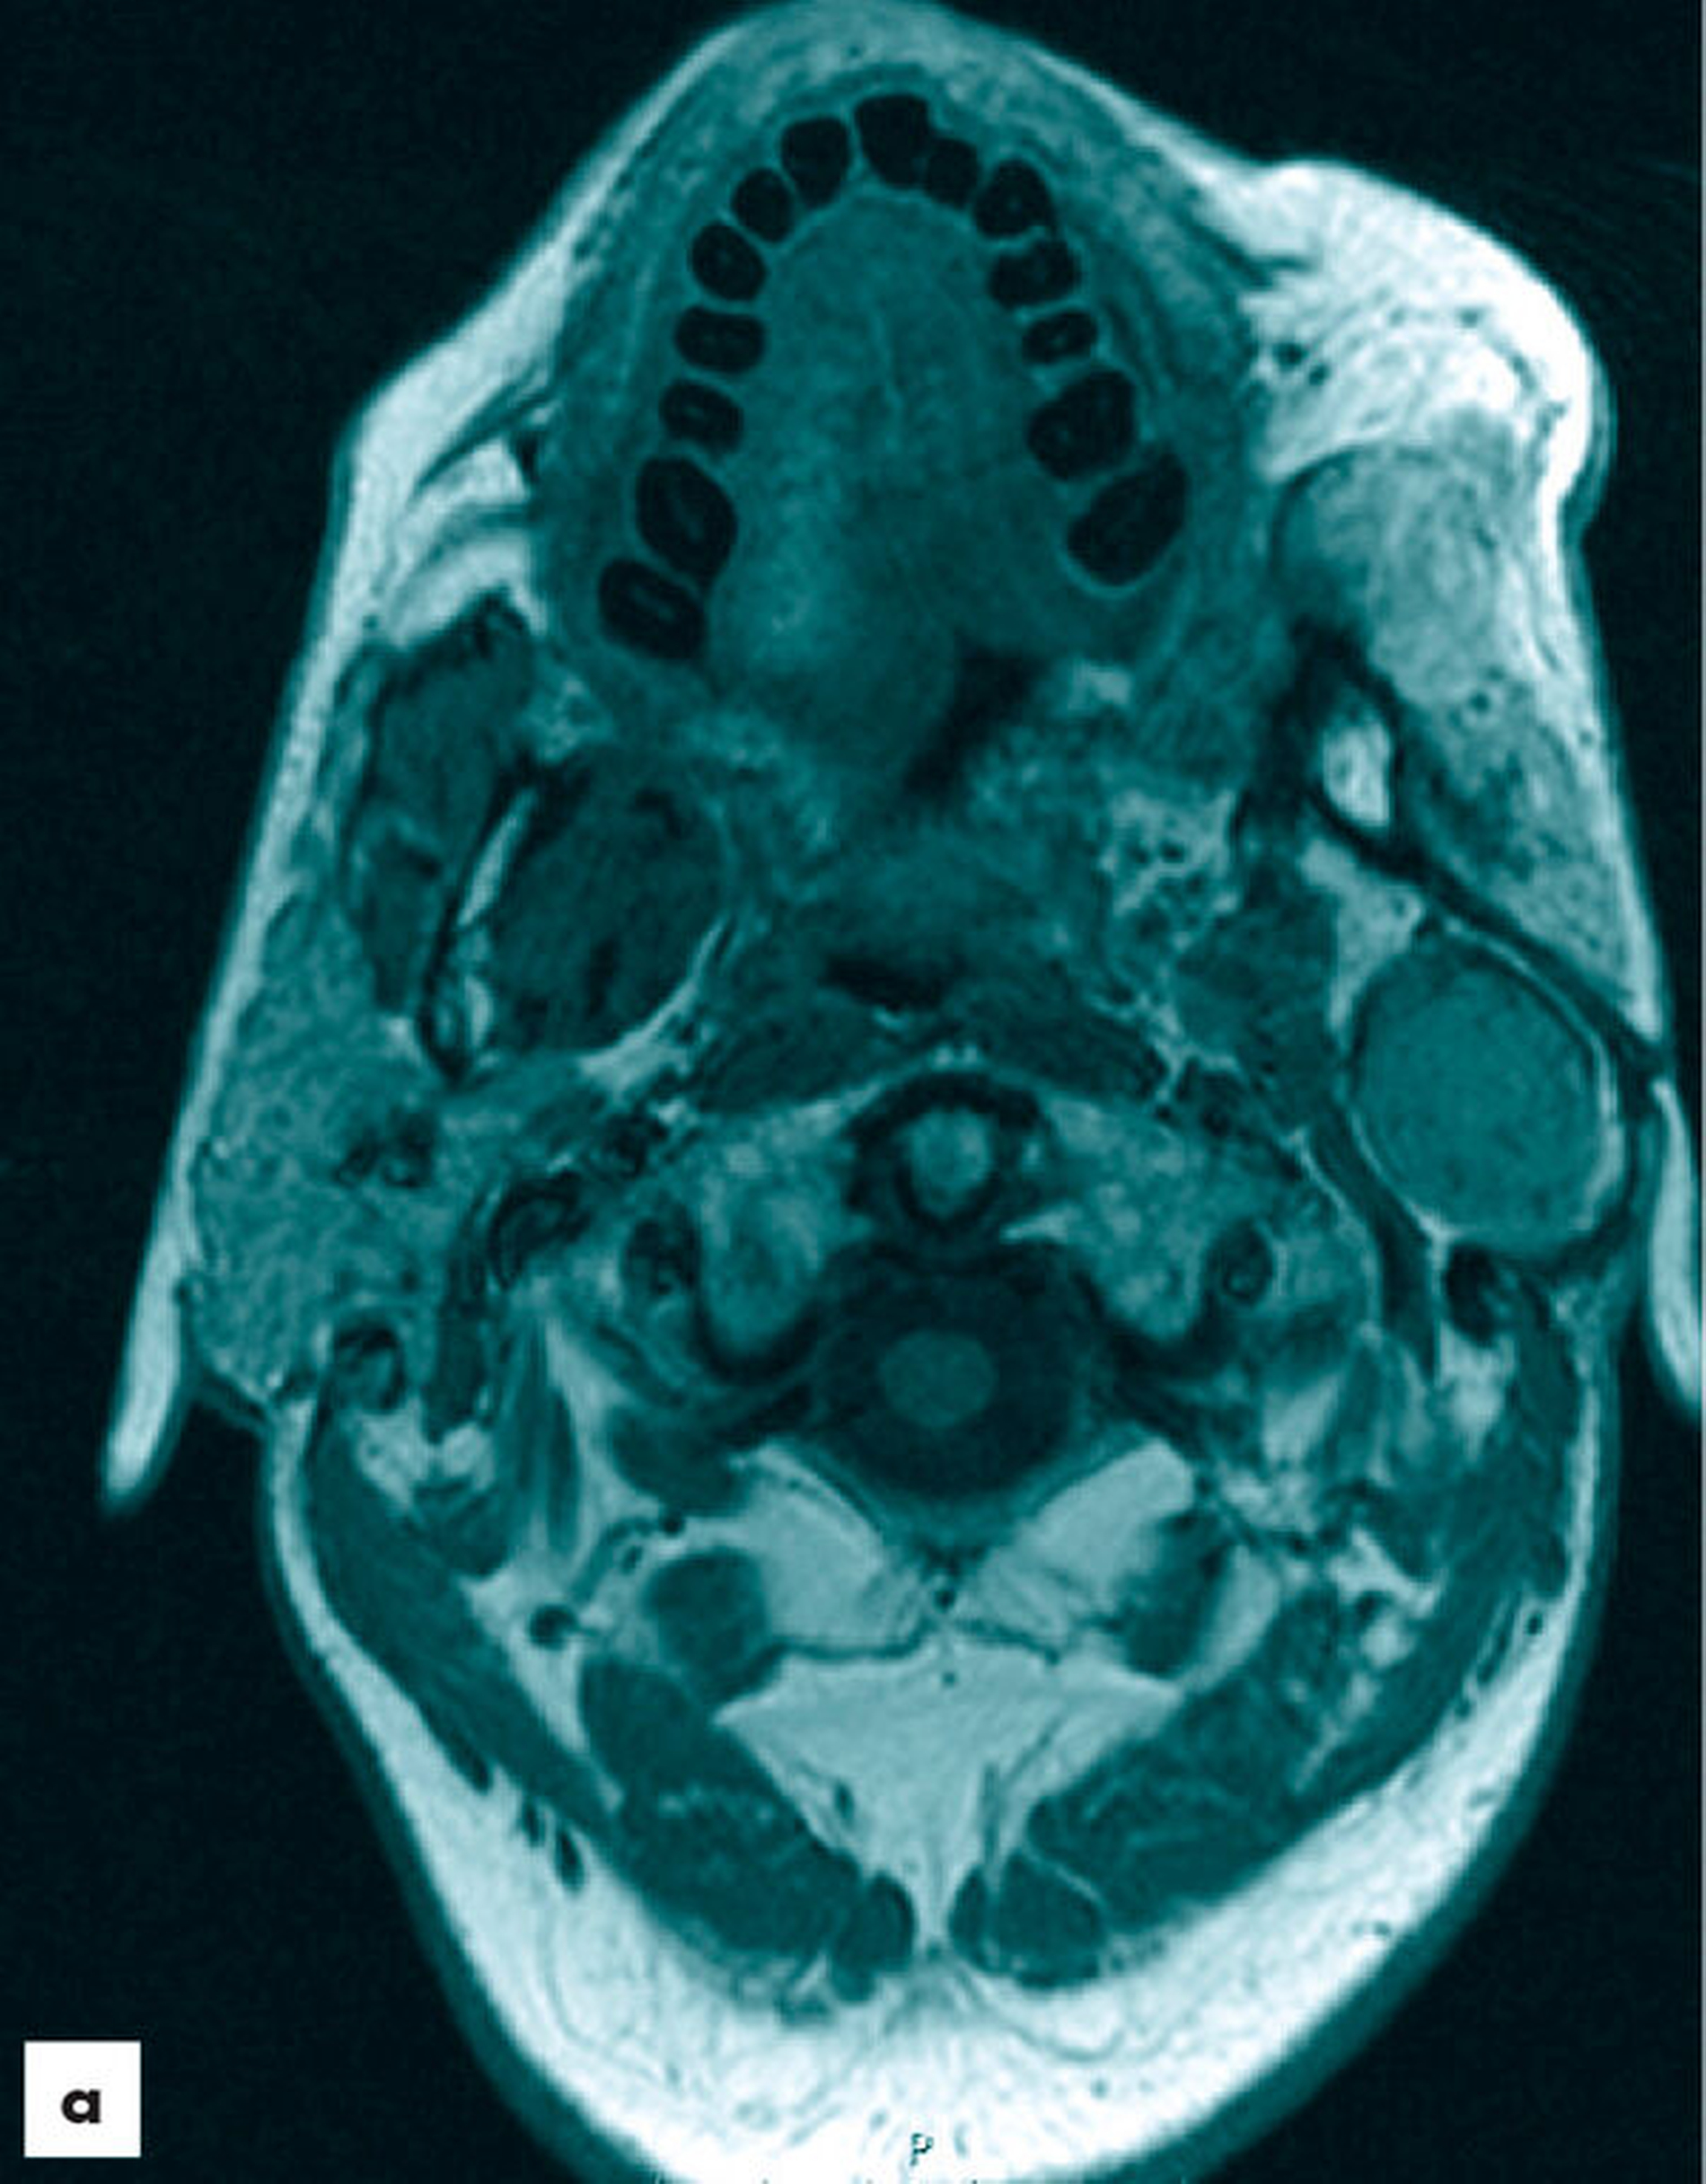

Sonografisch zeigte sich eine gut begrenzte, homogene, hyposonore Raumforderung ohne Nachweis auf eine Hypervaskularisation. Sonomorphologisch bestand damit der Verdacht auf einen gutartigen Speicheldrüsentumor. Zur weiteren Abklärung wurde eine Magnetresonanztomografie durchgeführt. Hierin stellte sich ein circa 4 cm x 3 cm großer, gut abgrenzbarer Tumor unterhalb des linken Ohres dar. Der Tumor zeigte eine Kontrastmittelaufnahme mit homogener Verteilung (Abbildung 2). Auffällige Lymphknoten kamen nicht zur Darstellung. Medial der Unterkieferrekonstruktion zeigte sich ein Parotisrest, der in Verbindung zu der Raumforderung stand. Bildmorphologisch entsprach der Befund einem monomorphen Adenom.